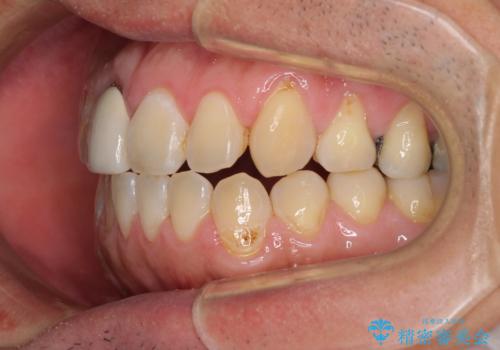

前歯のデコボコとクロスバイトをインビザライン矯正で改善

- 前歯のデコボコと上下のクロスバイトを気にして来院された患者様です。

インビザラインを用い、IPR(歯と歯の間を削る)と歯列全体を拡大させることで、歯並びを整えていくこととしました。

上の前歯が下の前歯を乗り越える際、奥歯がほとんど咬めない時期があり、乗り越えた後も、インビザライン特有の奥歯の咬みにくさが続きました。

咬み合わせ改善のために治療期間を要しましたが、最終的に奥歯はしっかりと咬めるようになりました